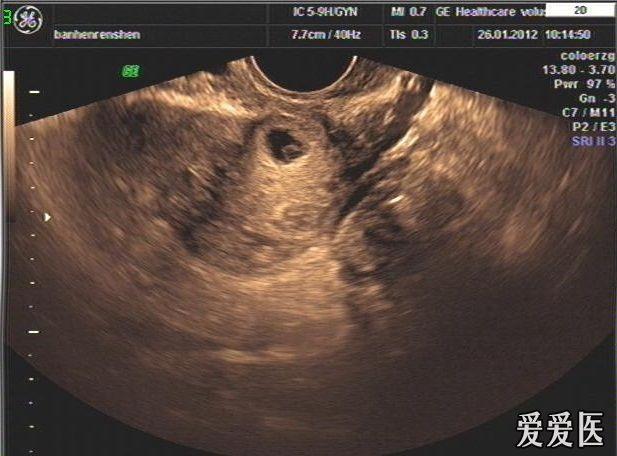

这是我这个月见到的第二例了切口妊娠了,不知道和手术有

图片尺寸617x456